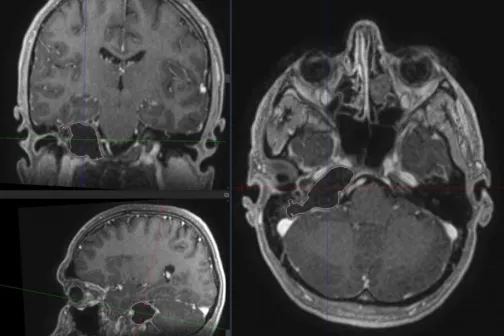

Imagine 20/07/2022 -19:03 Sănătate Premieră medicală în țara noastră! Medicii moldoveni au operat cu succes o tumoare craniană cu localizare profundă